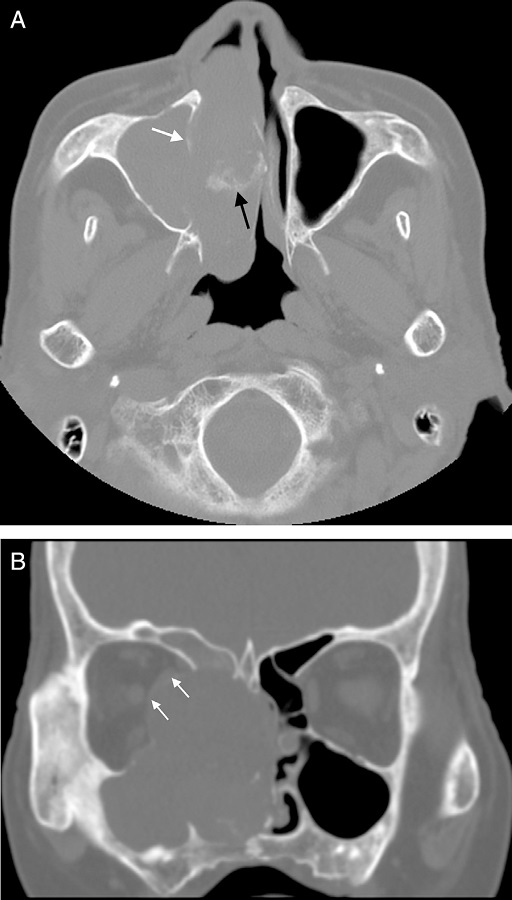

Diagnostic imaging included CT and MRI. The coronal and axial CT images showed a soft-tissue mass of right ethmoidal sinus, involving the right maxillary sinus, right frontal sinus and right nasal cavity. Bone erosion was observed in the right lamina of ethmoidal cells. The soft-tissue mass invaded the bony wall of right orbit and compressed the right eyeball (Fig. 1). MRI demonstrated the same appearances (Fig. 2). In additional, the mucous membrane of left ethmoidal sinus and bilateral sphenoid sinus were also compromised. Contrast-enhanced MRI confirmed heterogeneous enhancement of the lesion. Striped low-signal intensity was seen in the lesion.

The most common CT features are aggressive bone destruction and compressive bony absorption of sinus wall. The lesion easily erodes ipsilateral orbital medial wall in ethmoidal cells. In our case, ipsilateral orbital medial was destroyed and medial rectus and optic nerve were compressed to right side. On CT, the soft tissue mass shows isodensity or low density. Calcification foci can be found in some lesions.1 Striped calcification was found in our case. The tumor shows inhomogeneous iso-hyperintensity on T1WI, and mixed signal on T2WI. The collagenous fiber is hypointense while the liquefaction necrosis and mucoid degeneration are hyperintense on T2WI. Contrast-enhanced MRI confirmed homogeneous enhancement of the solid portion of lesion. The liquefaction necrosis and cystic degeneration are more significant in UHPS than other soft tissue tumors. The bigger the mass is, more common liquefaction necrosis and cystic degeneration are.8

Based on our case and literatures,1-3,5,6 we found the following imaging features of UHPS in the paranasal sinuses and nasal cavity: (i) the lesion fills up the whole paranasal sinus, (ii) aggressive bone destruction of sinus wall, (iii) erodes ipsilateral orbital medial wall, (iv) collagenous fiber, (v) homogeneous enhancement of the solid portion of lesion, (vi) liquefaction necrosis and cystic degeneration, and (vii) calcification.